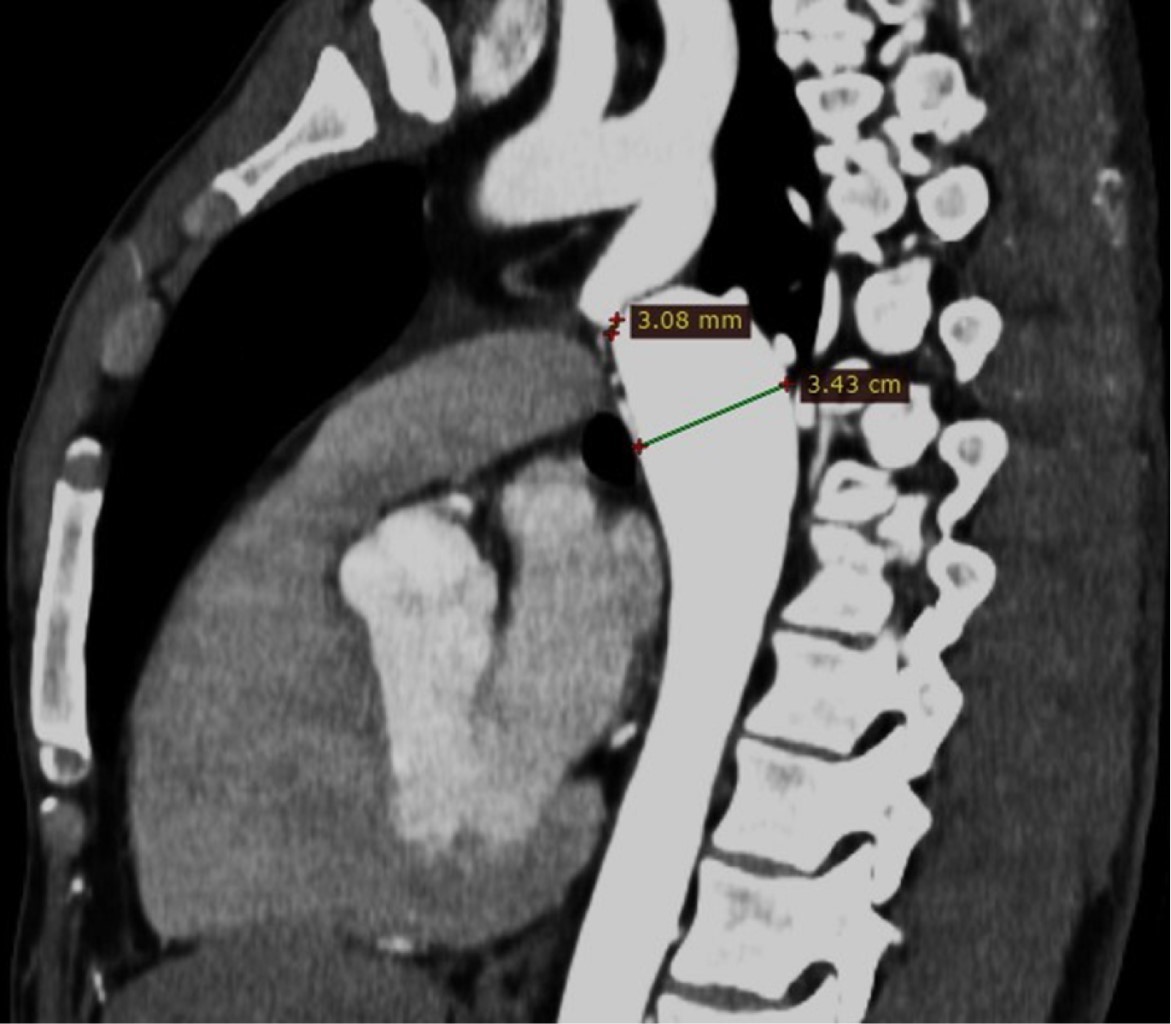

Coartación aórtica asociada a válvula aórtica bicúspide complicada con aneurisma aórtico postdisección

Sánchez-Amaya DJ, Godínez-Córdova LB, López-Lizárraga MÁ, Araiza-Garaygordobil D, Arias-Mendoza A

coartación aórtica, disección aórtica crónica, aneurisma aorta ascendente, válvula aórtica bicúspide.

La coartación aórtica es un trastorno congénito que afecta no solamente a la aorta, sino que también puede asociarse a válvula aórtica bicúspide y predispone a síndromes aórticos. Se reporta el caso de un paciente de 28 años de edad con hipertensión secundaria debido a coartación aórtica postductal asociada a válvula aórtica bicúspide que a su vez presentó disección crónica de la aorta ascendente. La coexistencia de enfermedad valvular aórtica, así como múltiples condiciones aórticas, es una situación rara que requiere una evaluación altamente especializada para garantizar un resultado favorable. El tratamiento se estableció en dos fases: aortoplastia con colocación de stent y luego cirugía de reemplazo aórtico y valvular, con una recuperación favorable.

Figura 1